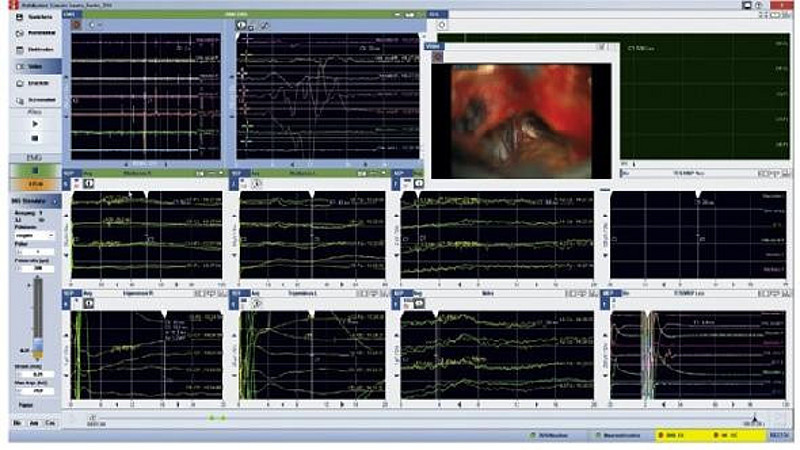

OBEN: MRT mit Akustikusneurinom, Mitte: Sicht durch das OP-Mikroskop, Unten: Billdschirm des Neuromonitoring